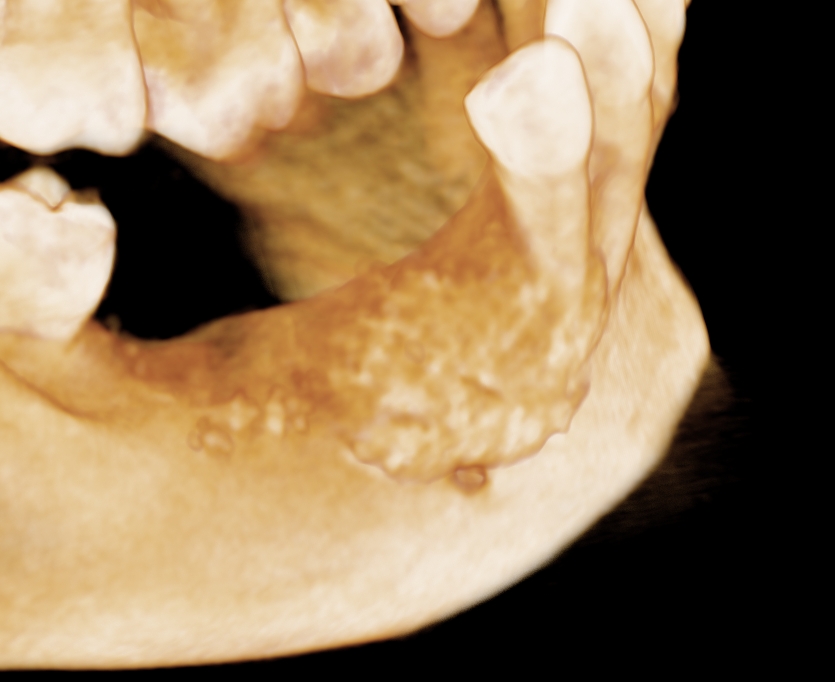

Ryc. 11. Rekonstrukcja 3D w 10 dobie po zabiegu. Cement utrzymuje nadany kształt w

ubytku kostnym.